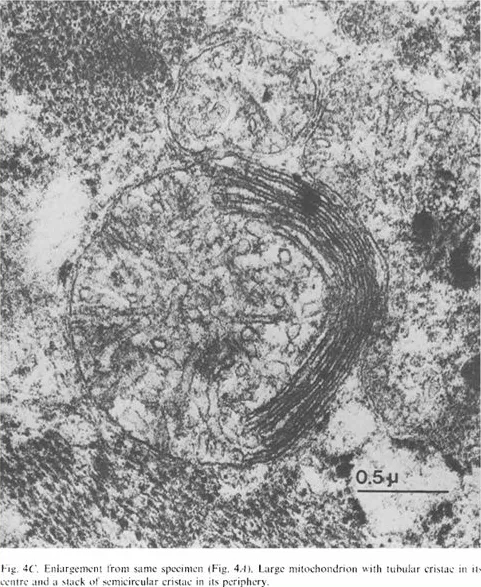

Barth综合征是一种比较“新”的疾病。1983年,荷兰阿姆斯特丹大学医院儿科医生Peter Barth报道了一个跨越五代人的大家系,其中男孩大多在婴幼儿期夭折,有些死于败血症,有些死于心力衰竭。女孩则表型正常。这种遗传模式是典型的X染色体连锁遗传病。Barth认真研究了这个家系,对死亡的患儿进行了尸检,对存活的患儿开展了细致的生化、血液学、和组织学检查。最终发现,患儿肌肉组织中线粒体的结构奇特,且产生能量的关键结构--呼吸链--功能异常 [1]。这一发现让人类第一次认识到X染色体连锁的线粒体病--Barth综合征。

Barth医生拍摄的患儿心肌中异常线粒体的电子显微镜照片。来源:[1]

经过数年探索,如今已基本阐明疾病病因。心磷脂仅在线粒体内膜中从头合成,最初是不成熟的形式,其中脂肪链的长度与饱和度各不相同。随后心磷脂要经过一个成熟过程,在tafazzin等磷脂酰基转移酶的催化下,用亚油酸这种常见的脂肪酸取代不对称脂肪酸,经过多次脱酰基-再酰基化反应,最终形成成熟的、对称的心磷脂 [6]。在健康人的心脏和肌肉细胞中,80%的心磷脂都是这种成熟形式。在Barth综合征患者中,成熟的心磷脂严重缺乏,而大量未成熟的心磷脂累积或被降解。这进一步导致了线粒体内膜嵴结构异常以及呼吸链功能障碍,这是患者出现心脏等器官损伤的核心原因。